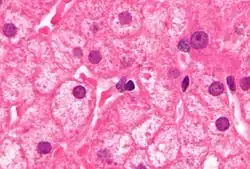

El virus de la hepatitis B interfiere fundamentalmente con las funciones del hígado, al replicarse en las células hepáticas, los hepatocitos. El receptor responsable del reconocimiento del virus en dichas células no se ha identificado aún, aunque hay evidencias de que el receptor en el virus de la hepatitis B del pato (estrechamente relacionado al virus humano) es la carboxipeptidasa D.[4] Los viriones de VHB (las partículas de Dane) se unen a la célula huésped mediante el dominio preS del antígeno de superficie viral, y son internalizados mediante endocitosis. Los receptores de PreS se expresan sobre todo en hepatocitos, pero también se han detectado ADN y proteínas virales en sitios extrahepáticos, lo que sugiere que tal vez también existan receptores para el VHB en células no hepáticas.[5]

Durante la infección con el VHB, la respuesta inmune del huésped es la responsable tanto de la eliminación del virus como del daño hepático. Aunque la respuesta innata no juega un papel significativo en estos procesos, la respuesta adaptativa, sobre todo los linfocitos T citotóxicos (CTLs) específicos contra el virus, contribuye a la mayor parte del daño hepático y a la eliminación de la infección por VHB. Los CTLs eliminan la infección por VHB mediante la destrucción de las células infectadas y la producción de citokinas antivirales, que se utilizan para purgar VHB de los hepatocitos aún viables.[6] Aunque el daño hepático es iniciado y mediado por los CTLs, células inflamatorias no específicas para el antígeno pueden empeorar la inmunopatología inducida por los CTLs, y las plaquetas activadas en el sitio de la infección pueden facilitar la acumulación de CTLs en el hígado.[7]